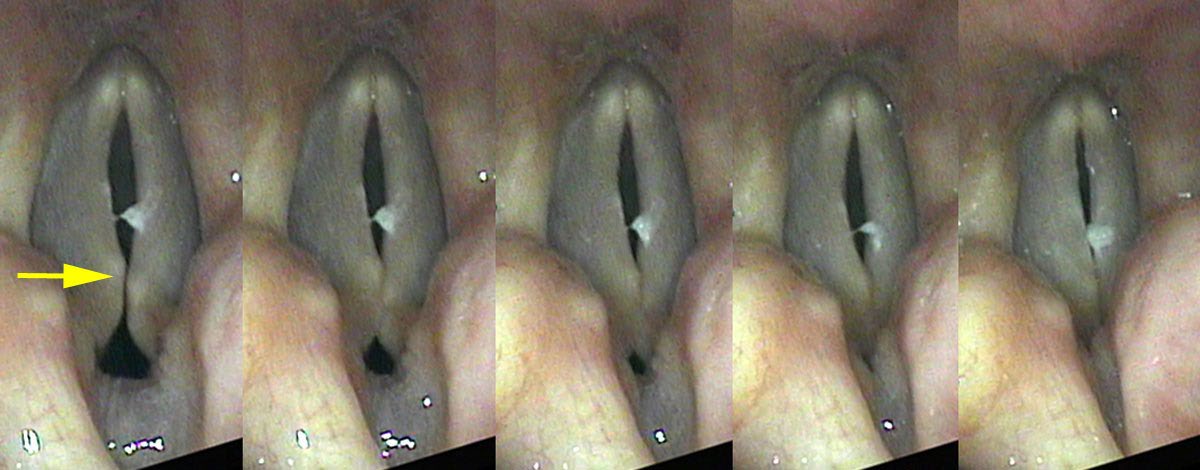

Vocal underdoers — people who rate 1, 2, or 3 on the talkativeness scale — suffer from deterioration of the thyroarytenoid (TA) muscle. The surface mucosa is fine; it is the muscle mass within the vocal cord that responds to lack of use with atrophy and loss of bulk. This is why the condition is often described as bowing — from above, the thin cords curve away from each other even when the speaker is trying to close them, leaving a characteristic spindle-shaped gap.

Diagnosing Atrophy on Vocal Capabilities Testing

On swelling testing at soft volumes, two findings emerge. High in the pitch range — where the CT muscle is engaged and the cords are stretched and taut — the patient can fairly easily make a soft sound without onset delays. As he progresses lower and lower in pitch, he is forced to relax the CT muscle and the bowing gap gets larger and larger. At some point he is unable to make any sound, as the air simply passes through the gap without setting the cords vibrating. The cut-off is less precise than the sharp note-specific onset delay of vocal nodules, because the gap grows progressively rather than abruptly.